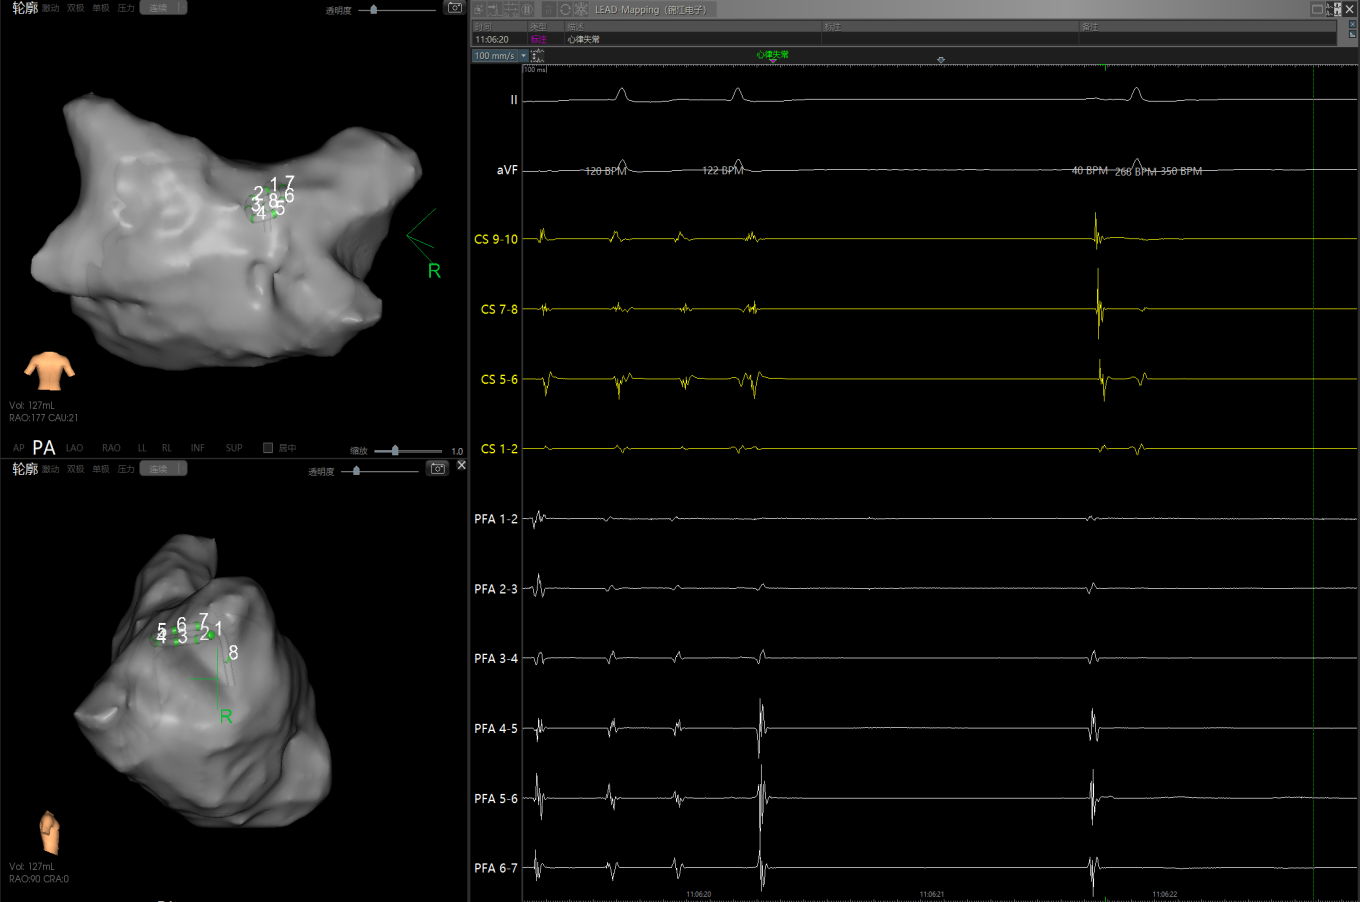

图1 患者因心功能差行电复律,窦律无法维持

经充分术前评估及准备后,该患者手术在抗心衰药物持续静脉泵入、高流量吸氧支持下及麻醉、护理团队的通力配合下进行,由薛建颖、崔明亮主治医师具体实施。术中通过右侧股静脉送入心腔内超声至右心房,排除左房血栓后成功指导房间隔穿刺,沿可调弯鞘管送入锦江心脏脉冲电场消融导管至左房,构建左房三维解剖模型并行基质标测,标测显示左房基质差,分别行左侧、右侧肺静脉及后壁BOX消融。消融参数:1800v,400ms,400μs,共放电消融140次(消融右肺静脉时转复为窦性心律),验证双肺静脉均隔离。术后重新标测显示所有肺静脉均已急性阻滞,消融效果理想,肺静脉前庭损伤范围也达到了预期的标准,同时心腔内超声监测未见明显心包积液。手术仅用时30分钟,时间明显缩短,手术过程精准高效。术后患者恢复情况良好,维持窦性心律。